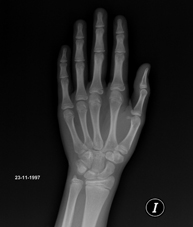

- Bone age X-ray

X-ray examination of the hand to assess the patient’s age based on the development of the bones and to determine if there is a delay or growth greater than that corresponding to the patient’s age.